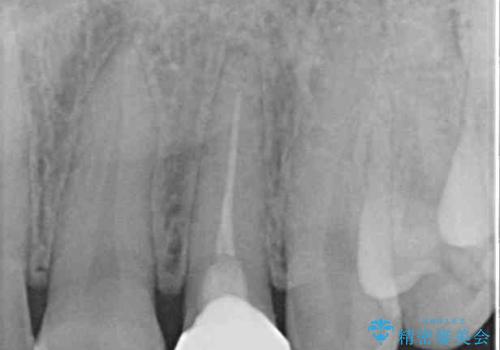

- 根管治療後に10年以上経過し、変色した前歯を気にして来院された患者様です。

根管治療はやり直さずに、ファイバーポストを使用した土台を植立してオールセラミッククラウンにて補綴することとしました。